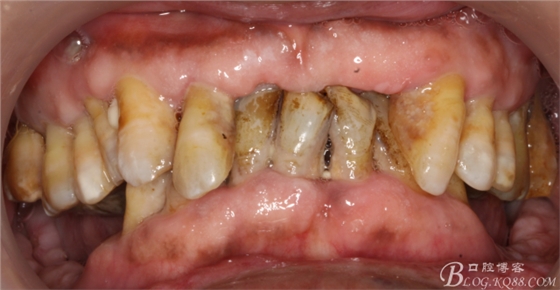

病人上前牙缺失,下頜前牙伸長(zhǎng)已經(jīng)咬到上頜牙槽脊,看x線片

牙槽骨嚴(yán)重吸收,全口牙還剩下21顆牙,但是 在1度松動(dòng)的牙齒只有12顆牙,其它牙都在2度到3度松動(dòng)之間

上頜--15、13、23、24、25

下頜--44、43、42、41、32、33、34